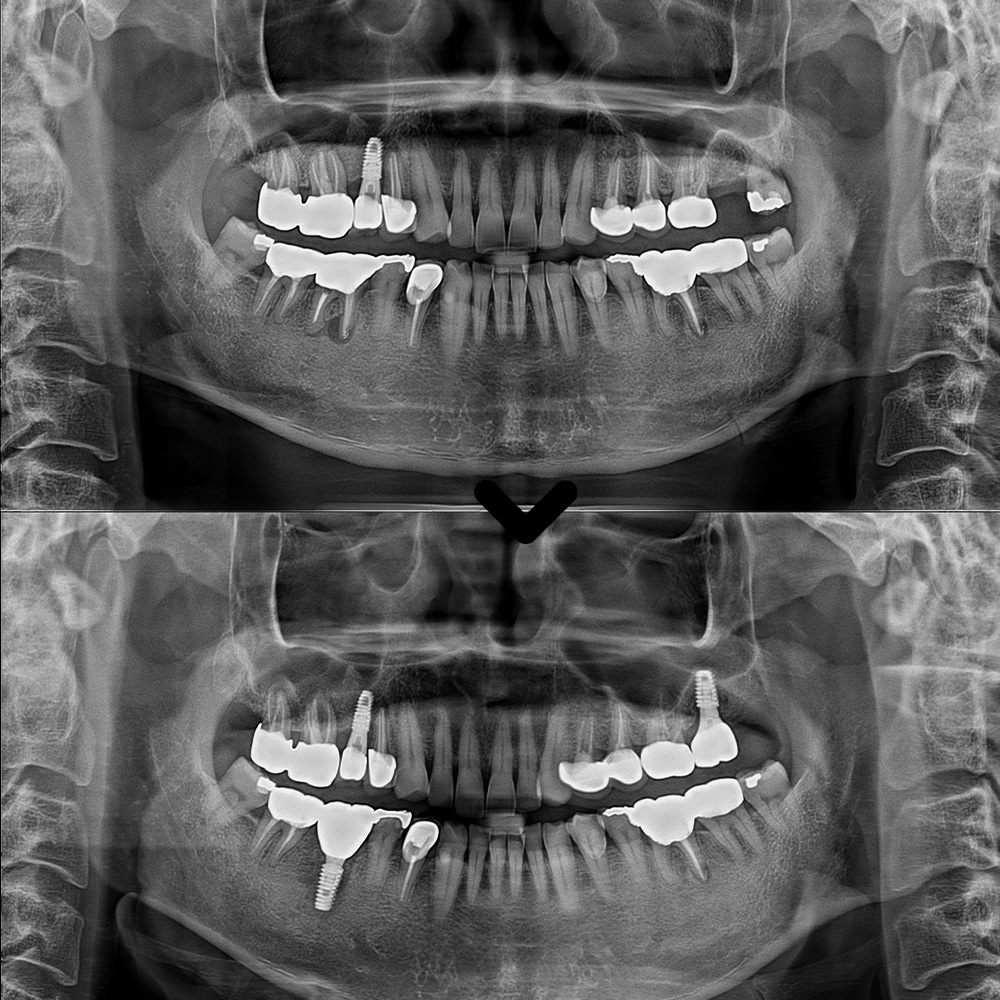

이번에 내원하신 환자분은

왼쪽 위 어금니 없이 지내신지 꽤 되셨고

전체적인 검진도 받아보기 위해

본원에 내원해 주셨습니다.

확인해 보니,

왼쪽 위 어금니의 상실이 있었고

사랑니도 있었습니다.

또한 오른쪽 아래

첫번째 큰 어금니 뿌리 끝으로

염증이 크게 잡혀있는 것을

확인 할 수 있었습니다.

그 다음 치료는 오른쪽 아래로,

CT상에서도 보이는

뿌리 끝 염증과 충치로 인해

골소실이 진행될만큼

썩어있는 상태였습니다.

이후 먼저 왼쪽 위 임플란트 먼저

보철 작업을 시작하였습니다.

왼쪽 위가 마무리 된 후

이어서 아래쪽도 서울박사치과의 맞춤형 지대주와

최종 보철을 제작하여 맞춰보았습니다.

이렇게 전체적인 치료가

마무리 되었습니다.

마무리 후 사진입니다.